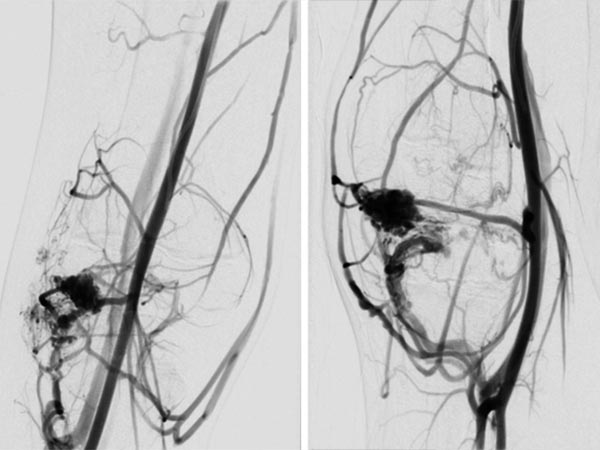

Digital subtraction angiography (DSA) of the knee (left AP projection, left lateral projection) shows an AVM with a rather spherical, aneurysmal nidus as well as another nidus intraosseously in the lateral tibial plateau. This very spherical, aneurysmal nidus together with the painful, progressive mass is suggestive of a PTEN hamartoma.